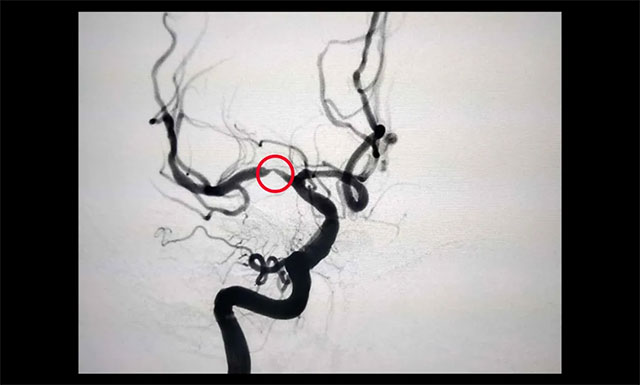

▲ 治疗后狭窄明显改善

经过与医院脑血管病病区主任张琪博士团队开展评估会诊,在医院DSA系统的支持下,由张琪博士为胡老伯行右侧大脑中动脉球囊扩张及支架置入手术。术中造影观察可见,狭窄明显改善,血流也随即恢复了通畅。